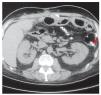

Dos meses después de su egreso, el paciente presentó dolor abdominal de predominio en hipocondrio derecho. Después de realizar ultrasonido de hígado y vías biliares y tomografía computarizada de abdomen, se estableció el diagnóstico de colecistitis aguda alitiásica y calcificación a nivel intestinal por lo que se realizó colecistectomía (Figura 1). Durante el procedimiento se identificó un proceso indurado a nivel intestinal, localizado a 10 cm de la ileostomía a nivel del borde mesentérico. No fue posible hacer el cierre de la ileostomía debido a las múltiples adherencias y al proceso óseo ya descrito. Seis meses después se realizó el cierre de la ileostomía y resección intestinal debido a este proceso óseo, de aproximadamente 10 cm de longitud (Figura 2), misma que se envió a estudio histopatológico que informó inflamación aguda y crónica en ileostomía, congestión vascular y área de metaplasia ósea distrófica asociada a inflamación crónica (Figura 3). El paciente evolucionó satisfactoriamente por lo que fue dado de alta al cuarto día de la cirugía.

¿ Figura 1. TC en la que se observa calcificación a nivel intestinal (señalada con la flecha), proximal a la boca de la ileostomía.

En el caso que aquí presentamos, el hecho de que al paciente se le hubiera colocado una malla de Vicryl® previamente, pudiera relacionarse con la presencia de esta neoformación ósea. Sin embargo, la osificación se encontraba muy cercana a la boca de la ileostomía y lejos de la malla como se observa en la imagen tomográfica, sin perder de vista que la malla fue colocada pre-peritoneal por arriba de la aponeurosis. Por esta razón, consideramos que el principal factor desencadenante de osificación heterotopica en nuestro paciente fue el número de reintervenciones quirúrgicas al que fue sometido debiéndose, principalmente al factor traumático, lo que pudiera apoyar la teoría de que existente sustancias no identificadas, probablemente secretadas por las células epiteliales con la capacidad de inducir osificación.4,6 Así mismo, se han postulado otras teorías, como el uso de nutrición parenteral, la presencia de una proteína hidrofóbica como agente causal activada por la propia inflamación local y la metaplasia osteoblástica de las células mesenquimatosas totipotenciales, inducida por la producción de mediadores de la inflamación en las células mesoteliales del peritoneo.2,9,10 No se ha esclarecido aún su intervención en el balance que debe existir entre los osteoblastos y osteoclastos para que se lleve a cabo la remodelación ósea.11 Recientemente en un estudio publicado por Sammour y colaboradores,12 partiendo del hecho de que el peritoneo es un órgano metabólicamente activo que interviene en las reacciones inflamatorias secundarias a estrés -como el quirúrgico- concluyeron que las intervenciones que disminuyen la respuesta peritoneal o bloquean la vía neuro-inmuno-humoral pueden ayudar a mejorar la recuperación posquirúrgica y reducir las complicaciones posoperatorias.